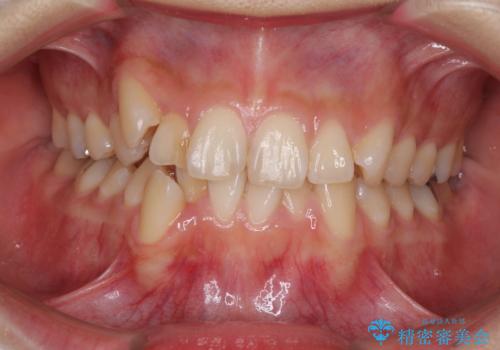

- 上下の八重歯を気にして来院された患者様です。

上下ともに八重歯の後ろの歯を1歯ずつ抜歯し、補助装置(リンガルアーチ)を用いて八重歯の位置を改善し、その後インビザラインにより矯正治療を行うこととしました。